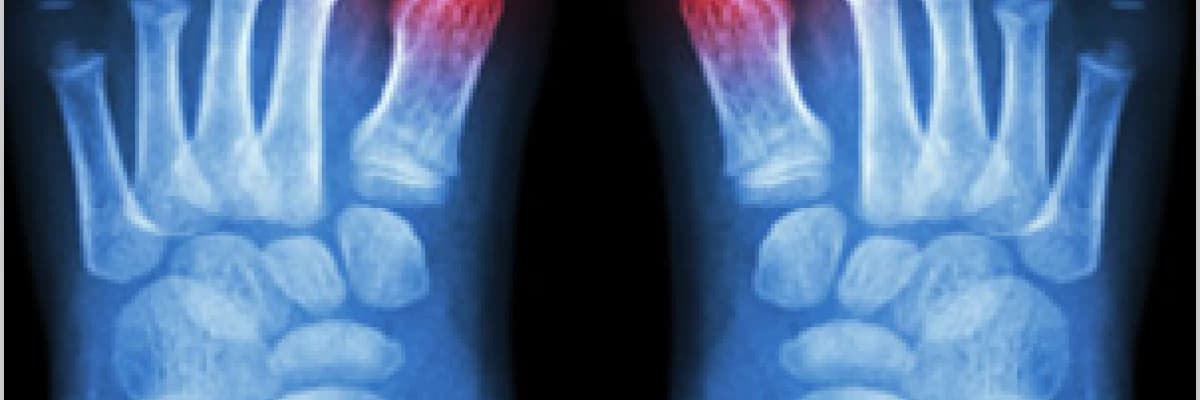

Radyolojik olarak eklem hasarının varlığı araştırılabilir. Tedavi bulgu olmayan ama ürik asit düzeyinin yüksek olduğu dönemde (%12 mg üzeri ) de düzenlenmelidir. Akut gut artritinde kolşisin ve kortizon olmayan antiromatizmal ilaçlar kullanılır.Ürik asit düzeyini kontrol etmek için allopurinol kullanılır ( akut atak dönemi dışında ).